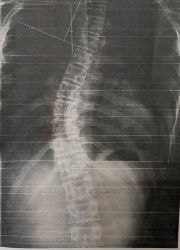

施術19回:コブ角33度

施術前:コブ角40度